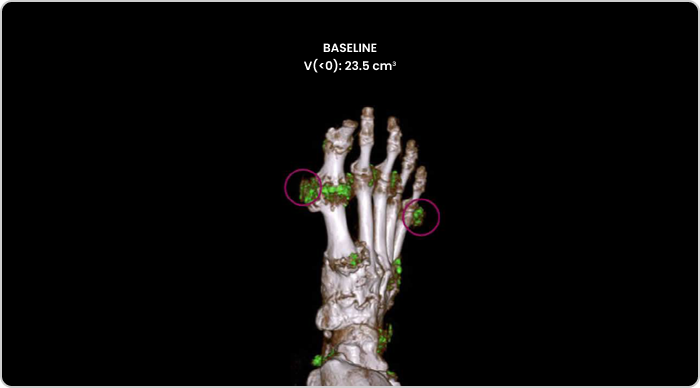

Image of tophi in hands with both visible and nonvisible buildup

PHOTO OF TOPHI BUILDUP

Image courtesy of Dr Jürgen Rech.

KRYSTEXXA is not indicated for the treatment of pain.

Dual Energy CT scan of hand showing visible and nonvisible buildup in gout patient

DECT OF URATE BUILDUP

DECT image courtesy of Dr. Jurgen Rech. Green areas indicate urate crystal buildup.

DECT, dual-energy computed tomography.

KRYSTEXXA is not indicated for treatment of pain.